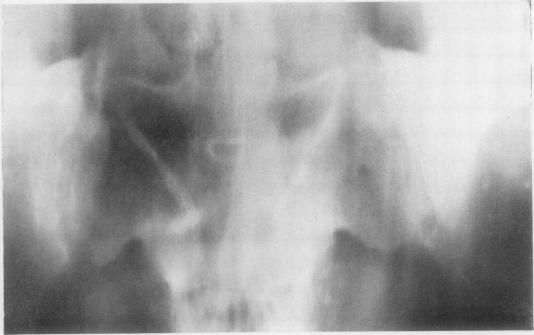

Radiological changes in the sacro-iliac joints and spine of patients with psoriatic arthritis and psoriasis.

Ann Rheum Dis. 1968 Jan;27(1):1-6. doi: 10.1136/ard.27.1.1.